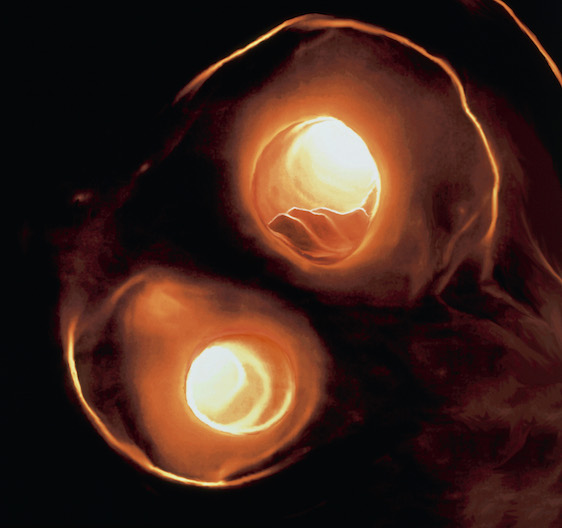

NEWS Newly introduced advanced ultrasound technology can be used to carefully study carotid arteries, the main blood vessels that supply the brain, and measure the effects of cholesterol-lowering drugs. A dissertation at Umeå University shows that ultrasound offers a radiation-free, easy-to-perform and cost-effective method to not only monitor the effect of treatment for deadly atherosclerosis disease but also to identify people at risk of a future brain stroke.

Picture of Pranvera Ibrahimi at Umeå University.By looking closely at features of the carotid plaques on the right and left sides of the neck, researchers have confirmed that atherosclerosis severity is similar in both sides of symptomatic patients. Also supporting the concept of atherosclerosis is a systemic disease, researchers found that measuring the normal arterial wall in the lower segments of the vessel could accurately predict atherosclerotic disease severity higher up in the carotid tree.

Atherosclerosis, which means hardening of the arteries, is caused by an accumulation of fat in artery walls, which leads to inflammation, hardening and eventually blockage of the blood vessel.  While medical treatment with cholesterol lowering medications improves the arterial wall disease, significant narrowing in of the lumen in symptomatic patients can only be treated surgically. In patients without atherosclerosis, ultrasound examination of the carotid arteries can be used to identify arterial wall disease before significant narrowing develops.